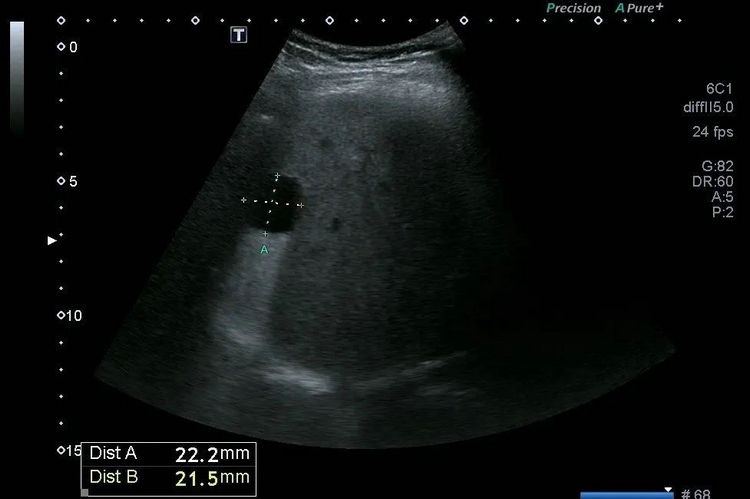

▲ 肝囊肿

局灶性病变是指肝脏局部出现的占位性病变,这里会分为两类,一种是良性病变,一种是恶性病变。良性病变包括肝囊肿、肝腺瘤、肝血管瘤及肝脏局灶性结节性增生(FNH)等等。肝囊肿是体检时最常见的局灶性病变,肝囊肿通常生长速度缓慢,一般小的囊肿(<5cm),不需要特殊处理,随着年龄增长,肝囊肿的数目和大小也会有所变化,通常是半年或是1年复查一次。当囊肿突然增大时,考虑出血或是感染,这时就需要及时进行干预。当囊肿较大,并且产生压迫症状(例如腹痛等),也应进行治疗。